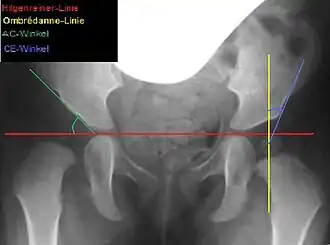

Red=Hilgenreiner line, yellow=Ombrédanne line, green=AC angle (dysplastic side), blue=CE angle (healthy side)

Lateral coverage is measured using the acetabular angle (AC angle) on a pelvic X-ray, defined as the angle between a horizontal line through the Y-sutures and a line along the acetabular rim. In healthy newborns, the AC angle is approximately 25°, decreasing to about 15° by age 6 and 11–12° by age 12.[6] Acetabuloplasty aims to correct the AC angle to these physiological values, achieving an anatomical reconstruction.[6]